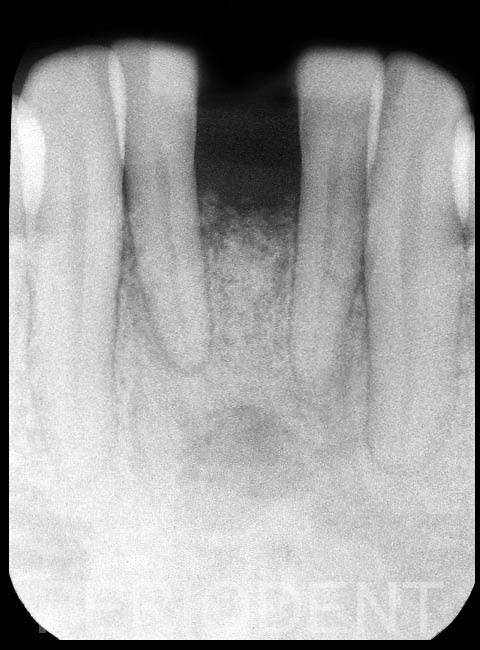

骨增生手術癒合後

骨增生手術後六個月,植牙時用迷你植體,並同時裝上臨時假牙,但沒有咬合接觸